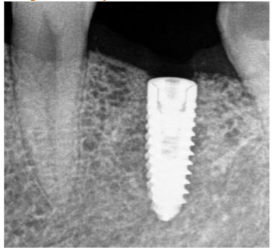

After a period of 5-month showing intraorally and radiographically the site from where bone core using trephine was taken for histological analysis; the same site where implant, Mis implant 3.75/11.5 was placed.

All sites healed uneventfully. There was no sign of post-operative infection. None of the patients showed any complications post-surgical. Additionally, none of the surgical sites needed additional hard or soft tissue grafting. Upon implant placement, the surgical sites showed appropriate healing as it is seen in any other grafted areas. Furthermore, there was adequate bucco-lingual width of the grafted for Implants placement. Implants placed showed satisfactory primary stability.